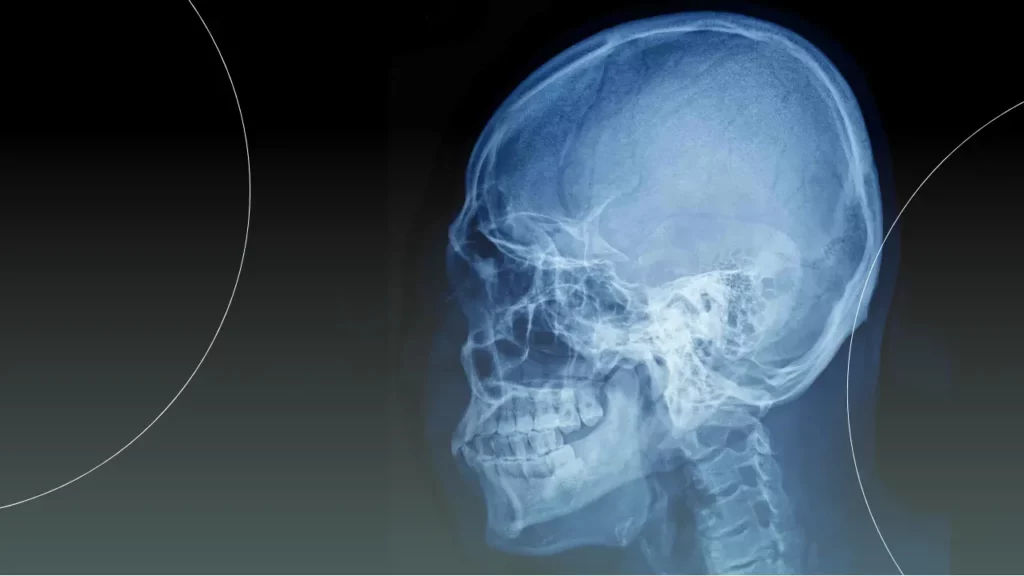

۲. رادیوگرافی سفالومتری لترال

این شاید مهم ترین عکس در میان انواع رادیوگرافی ارتودنسی باشد. سفالومتری، یک عکس نیمرخ (پروفایل) از کل جمجمه و صورت شماست. این تصویر، فقط یک عکس ساده نیست؛ بلکه یک نقشه مهندسی دقیق است که متخصص ارتودنسی با اندازه گیری زوایا و فواصل مختلف روی آن (که به آن آنالیز سفالومتری می گویند)، به اطلاعات حیاتی دست پیدا می کند.

- رابطه فک ها با هم و با جمجمه: آیا مشکل کجی دندان ها صرفاً دندانی است یا ریشه در ناهنجاری اسکلتی فک شما دارد؟ (مثلاً فک پایین شما جلوتر یا عقب تر از حالت نرمال است؟)

- الگوی رشد صورت: در بیماران نوجوان، این عکس به پیش بینی مسیر رشد آینده فک کمک کرده و به متخصص اجازه می دهد تا از این رشد برای هدایت درمان استفاده کند.

- زاویه دندان ها: زاویه قرارگیری دندان های جلویی نسبت به استخوان فک چگونه است؟ این اطلاعات برای طراحی یک لبخند زیبا و پایدار ضروری است.

- نیاز به جراحی فک: در موارد شدید، آنالیز سفالومتری مشخص می کند که آیا درمان ارتودنسی به تنهایی کافی است یا نیاز به جراحی فک نیز وجود دارد.

چون این عکس، امضای کار یک متخصص ارتودن-سی واقعی است. او فقط دندان ها را صاف نمی کند، بلکه به هماهنگی بین دندان، فک و کل چهره شما فکر می کند و سفالومتری تنها ابزاری است که این دید عمیق را به او می دهد.